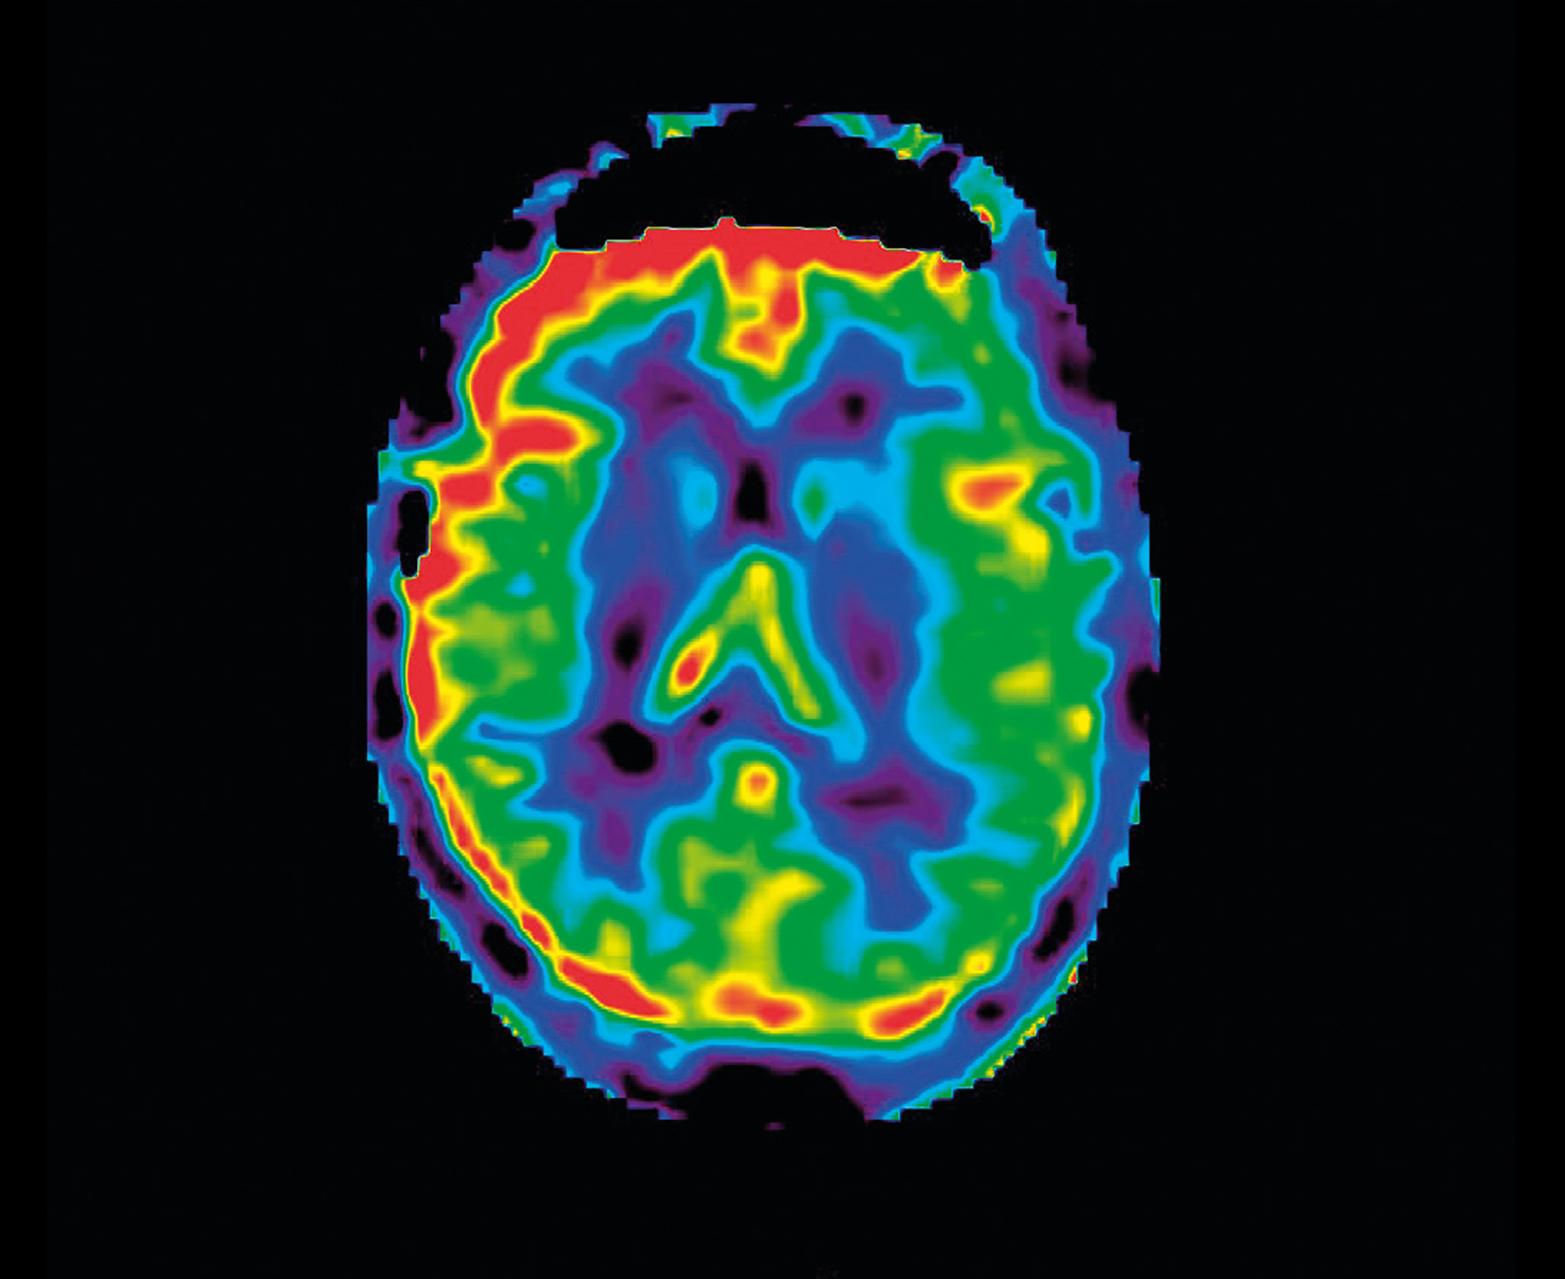

- Неинвазивная перфузия ASL для педиатрии и противопоказания почек

Неконтрастная перфузия ASL